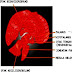

Kelenjar endokrirt terletak pada bagian tubuh yang terpisah, tetapi kerjanya paling mempengaruhi satu sama lain, terkoordinasi dalam satu kesatuan yang disebut sistem hormon (sistem endokrin). Kelenjar endokrin yang terdapat pada tubuh manusia terdiri atas beberapa macam, di antaranya adalah sebagai berikut.

Gambar 2.1 Letak kelenjar endrokrin utama pada pria dan wanita (http://www.bio.psu.edu/course/bio414/human body.html).